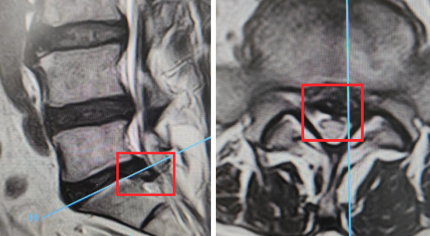

术前通过影像资料定位脱出髓质位置及大小,做到术区精确微创规划。

脊柱科主任尚军接诊后,综合李师傅的的腰部影像学检查和临床表现,确诊他为腰椎间盘突出,且椎间盘部分钙化,建议他在高倍显微镜下微创摘除脱出的腰椎间盘髓核。